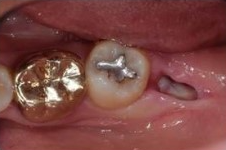

✅5일차 / 10일차

보통 일주일 정도 후부터 본격적으로

잇몸이 닫히기 시작합니다.

실밥 제거 후 발치구멍에

하얀 무언가가 얼핏 보입니다.

이는 음식물이나 염증이 아닌

정상적인 회복과정에 생기는 조직입니다.

5일차 / 10일차